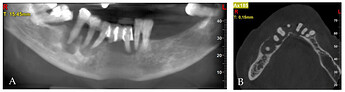

Pre-treatment CBCT: (A) panoramic view; (B) axial view; (C) cross-sections in position of teeth, respectively, 32; (D) 34; (E) 42; (F) 44; (G) 45; (H) 45.